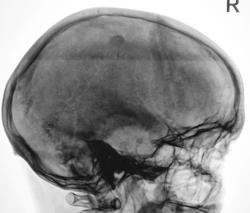

По боковому снимку, в проекции теменной области плотная округлая тень. Для уточнения характера изменений рекомендованя МРТ головы.С какой целью назначалось исследование?

Ответ таков: на снимках черепа есть подозрение на патологическое обызвествление. А теперь давайте гадать, что это. Обызвествление серпа или кальцинаты интракраниально. 50/50

Я бы описал обызвествление (вероятно, серпа) и рекомендовал консультацию невролога. Может, есть другие причины для головной боли, и кальцинат тут ни при чем? А невролог рекомендует то, что с его точки зрения нужно для пациента.

Я надеялся, что обызвествление серпа, даже пусть локальное, лучше должно быть видно на рентгенограмме, произведенной в прямой проекции...

Странное обызвествление для серповидного отростка - круглое такое... (Выше - он, согласен, а здесь - ?..) А в прямой проекции оно проекционно сливается с озерцом или растворилось в эмиссариях, надо полагать?..